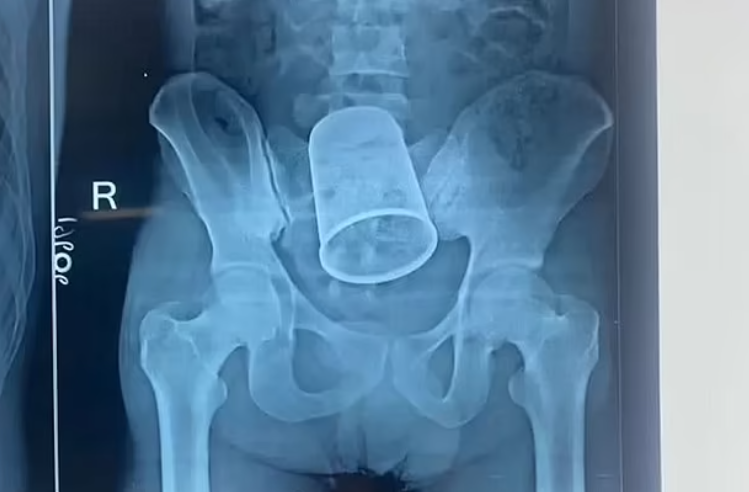

പാറ്റ്ന: യുവാവിന്റെ വയറ്റില് കുടുങ്ങിയ സ്റ്റീല് ഗ്ലാസ് രണ്ടര മണിക്കൂര് നീണ്ട ശസ്ത്രക്രിയയിലൂടെ പുറത്തെടുത്തു. പാറ്റ്ന, ബേട്ടിയ സ്വദേശിയായ റിതേഷ് കുമാറിന്റെ(22) വയറ്റില് നിന്നാണ് ഗ്ലാസ് പുറത്തെടുത്തത്. 5.5 ഇഞ്ച് വലിപ്പമുള്ള ഗ്ലാസാണ് വയറ്റില് കുടുങ്ങിയത്.

ശക്തമായ വേദനയെയും രക്തസ്രാവത്തെയും തുടര്ന്ന് ഒക്ടോബര് 4നാണ് റിതേഷിനെ പാറ്റ്ന മെഡിക്കല് കോളേജ് ആശുപത്രിയില് പ്രവേശിപ്പിച്ചത്. മദ്യപിച്ചെത്തിയ യുവാവിന്റെ ഗുഹ്യഭാഗത്ത് ചോരയൊലിക്കുന്നുണ്ടായിരുന്നു. ഗ്ലാസ് ഗുഹ്യഭാഗത്തു കൂടിയാണ് വയറിനുള്ളിൽ എത്തിയതെന്ന് ഡോക്ടർമാർ പറഞ്ഞു. ശസ്ത്രക്രിയ അപകടകരമായിരുന്നുവെന്നും എന്നാല് 11 ഡോക്ടര്മാരടങ്ങുന്ന സംഘം സുരക്ഷിതമായി ഗ്ലാസ് പുറത്തെടുത്തുവെന്നും ശസ്ത്രക്രിയക്ക് നേതൃത്വം നല്കിയ ഡോ. ഇന്ദ്ര ശേഖര് കുമാര് പറഞ്ഞു.